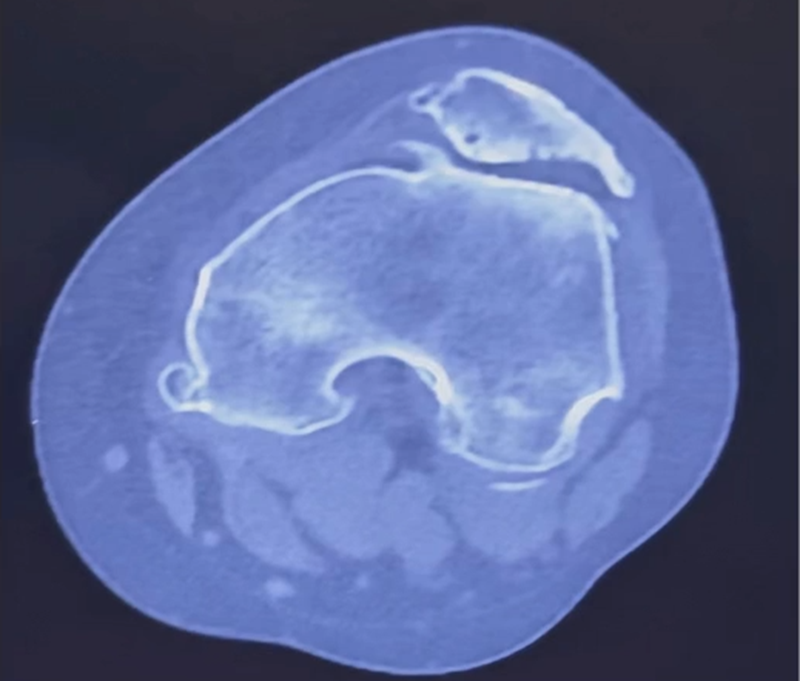

术前CT显示:髌骨与股骨外髁形成关节,周边有大量骨赘,软骨已经硬化,并伴有囊变。

术前CT